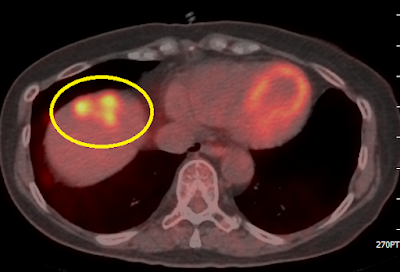

1.大腸癌女行病人,轉肝臟與肺,化療治療下仍持續緩慢的升高腫瘤指數,正子照影顯示主要轉移在肝臟,次要轉移在肺臟,經過高劑量放療(SBRT)與電熱療法(electric hyperthermia)有效減少腫瘤指數(ca199從190降到35)延緩疾病蔓延

2.三陰型女性患者,化療藥治療後只剩口服化療,正子照影顯示仍有肝轉移殘留,經過高劑量放療SBRT,CA153 從80降到25,同時放療時配合免疫營養多醣體,減緩疾病惡化速度。